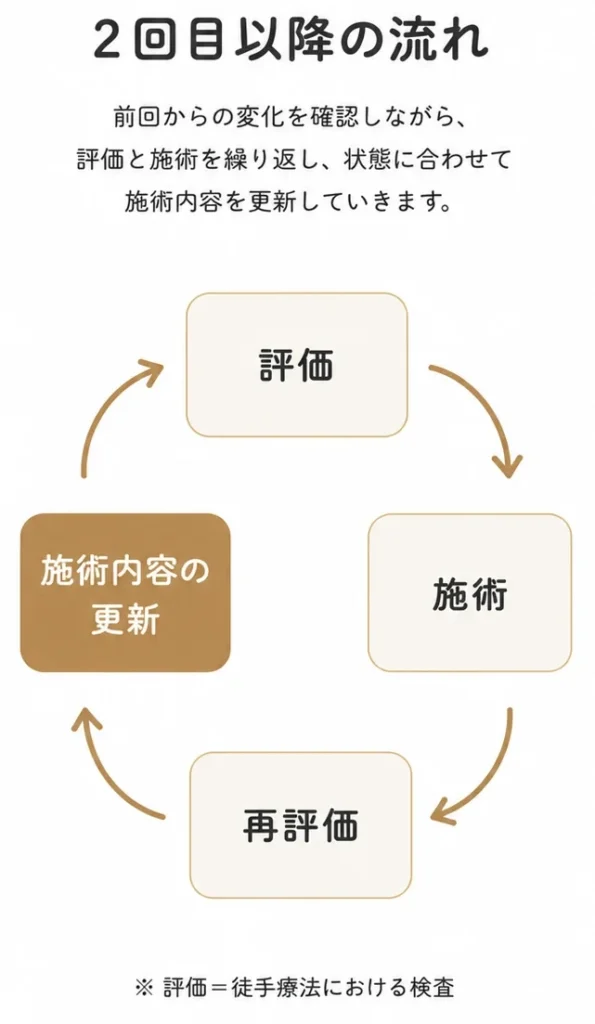

施術の流れ

症状箇所は同じでも、その理由はお一人おひとり異なります。

整体よしかでは、評価・施術・再評価・説明を大切にしています。